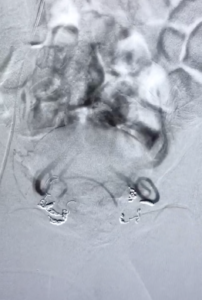

Bilan artères rectales supérieures avant embolisation